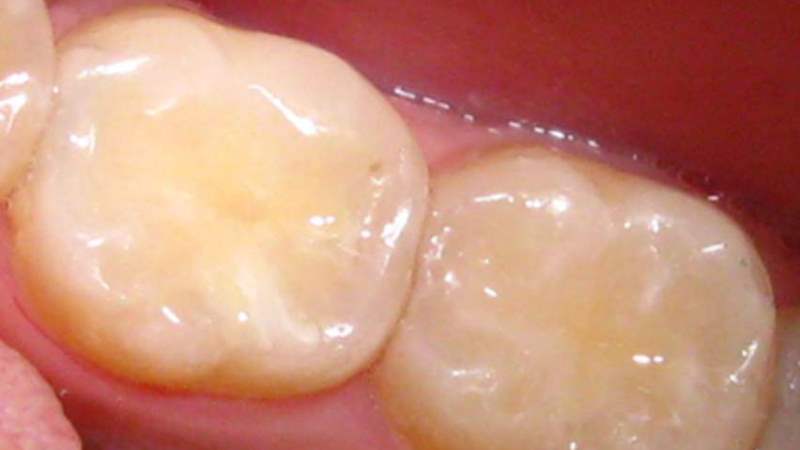

Пломбирование зуба и каналов является одной из наиболее востребованных стоматологических процедур. Обычно оно выполняется после лечения полости рта, зубов и десен, а также перед протезированием. Пломба помогает укрепить и частично восстановить поврежденную коронку, закрыть полость после удаления пульпы, создать опору для штифтов и искусственных зубов.

Современные стоматологические клиники все чаще используют фотополимерные и световые пломбы, которые цементируются слоями и моментально высыхают под воздействием УФ-лампы. Это позволяет прочно закрепить материал на зубной ткани. Однако, после такой процедуры возникает проблема питания. Обычно пломбирование зуба выполняется под местным наркозом, который продолжает действовать еще 2-3 часа после процедуры, вызывая онемение во рту. В связи с этим, не рекомендуется есть в первые часы после пломбирования. Это связано с риском получения ожогов или обморожений тканей из-за невозможности ощущать температуру пищи, искажением вкуса из-за нарушения работы рецепторов и повышенным риском травмирования мягких тканей при кусании и жевании. Некоторые стоматологи могут разрешать пациентам есть сразу после процедуры, но это является ошибкой, так как пациент должен быть осведомлен о возможных последствиях и нести ответственность за свои действия.